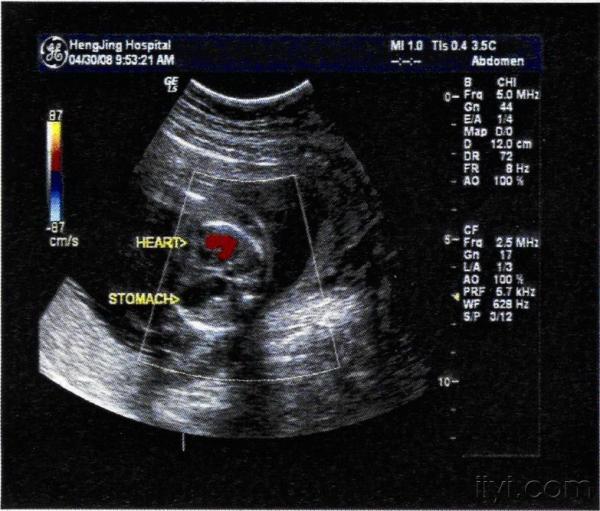

横膈膜是一张将胸腔与腹部分开并帮助呼吸的肌肉片。先天性膈疝是在横膈膜上有孔时发生的,因为它在子宫中没有正式形成。

横膈膜上有孔意味着腹部器官可以通过肌肉,挤压肺部,阻止肺部发育正常。孔可以出现在隔膜的任何一侧,但通常发生在左边。

先天性膈疝可在产前超声或婴儿出生后立即诊断出。